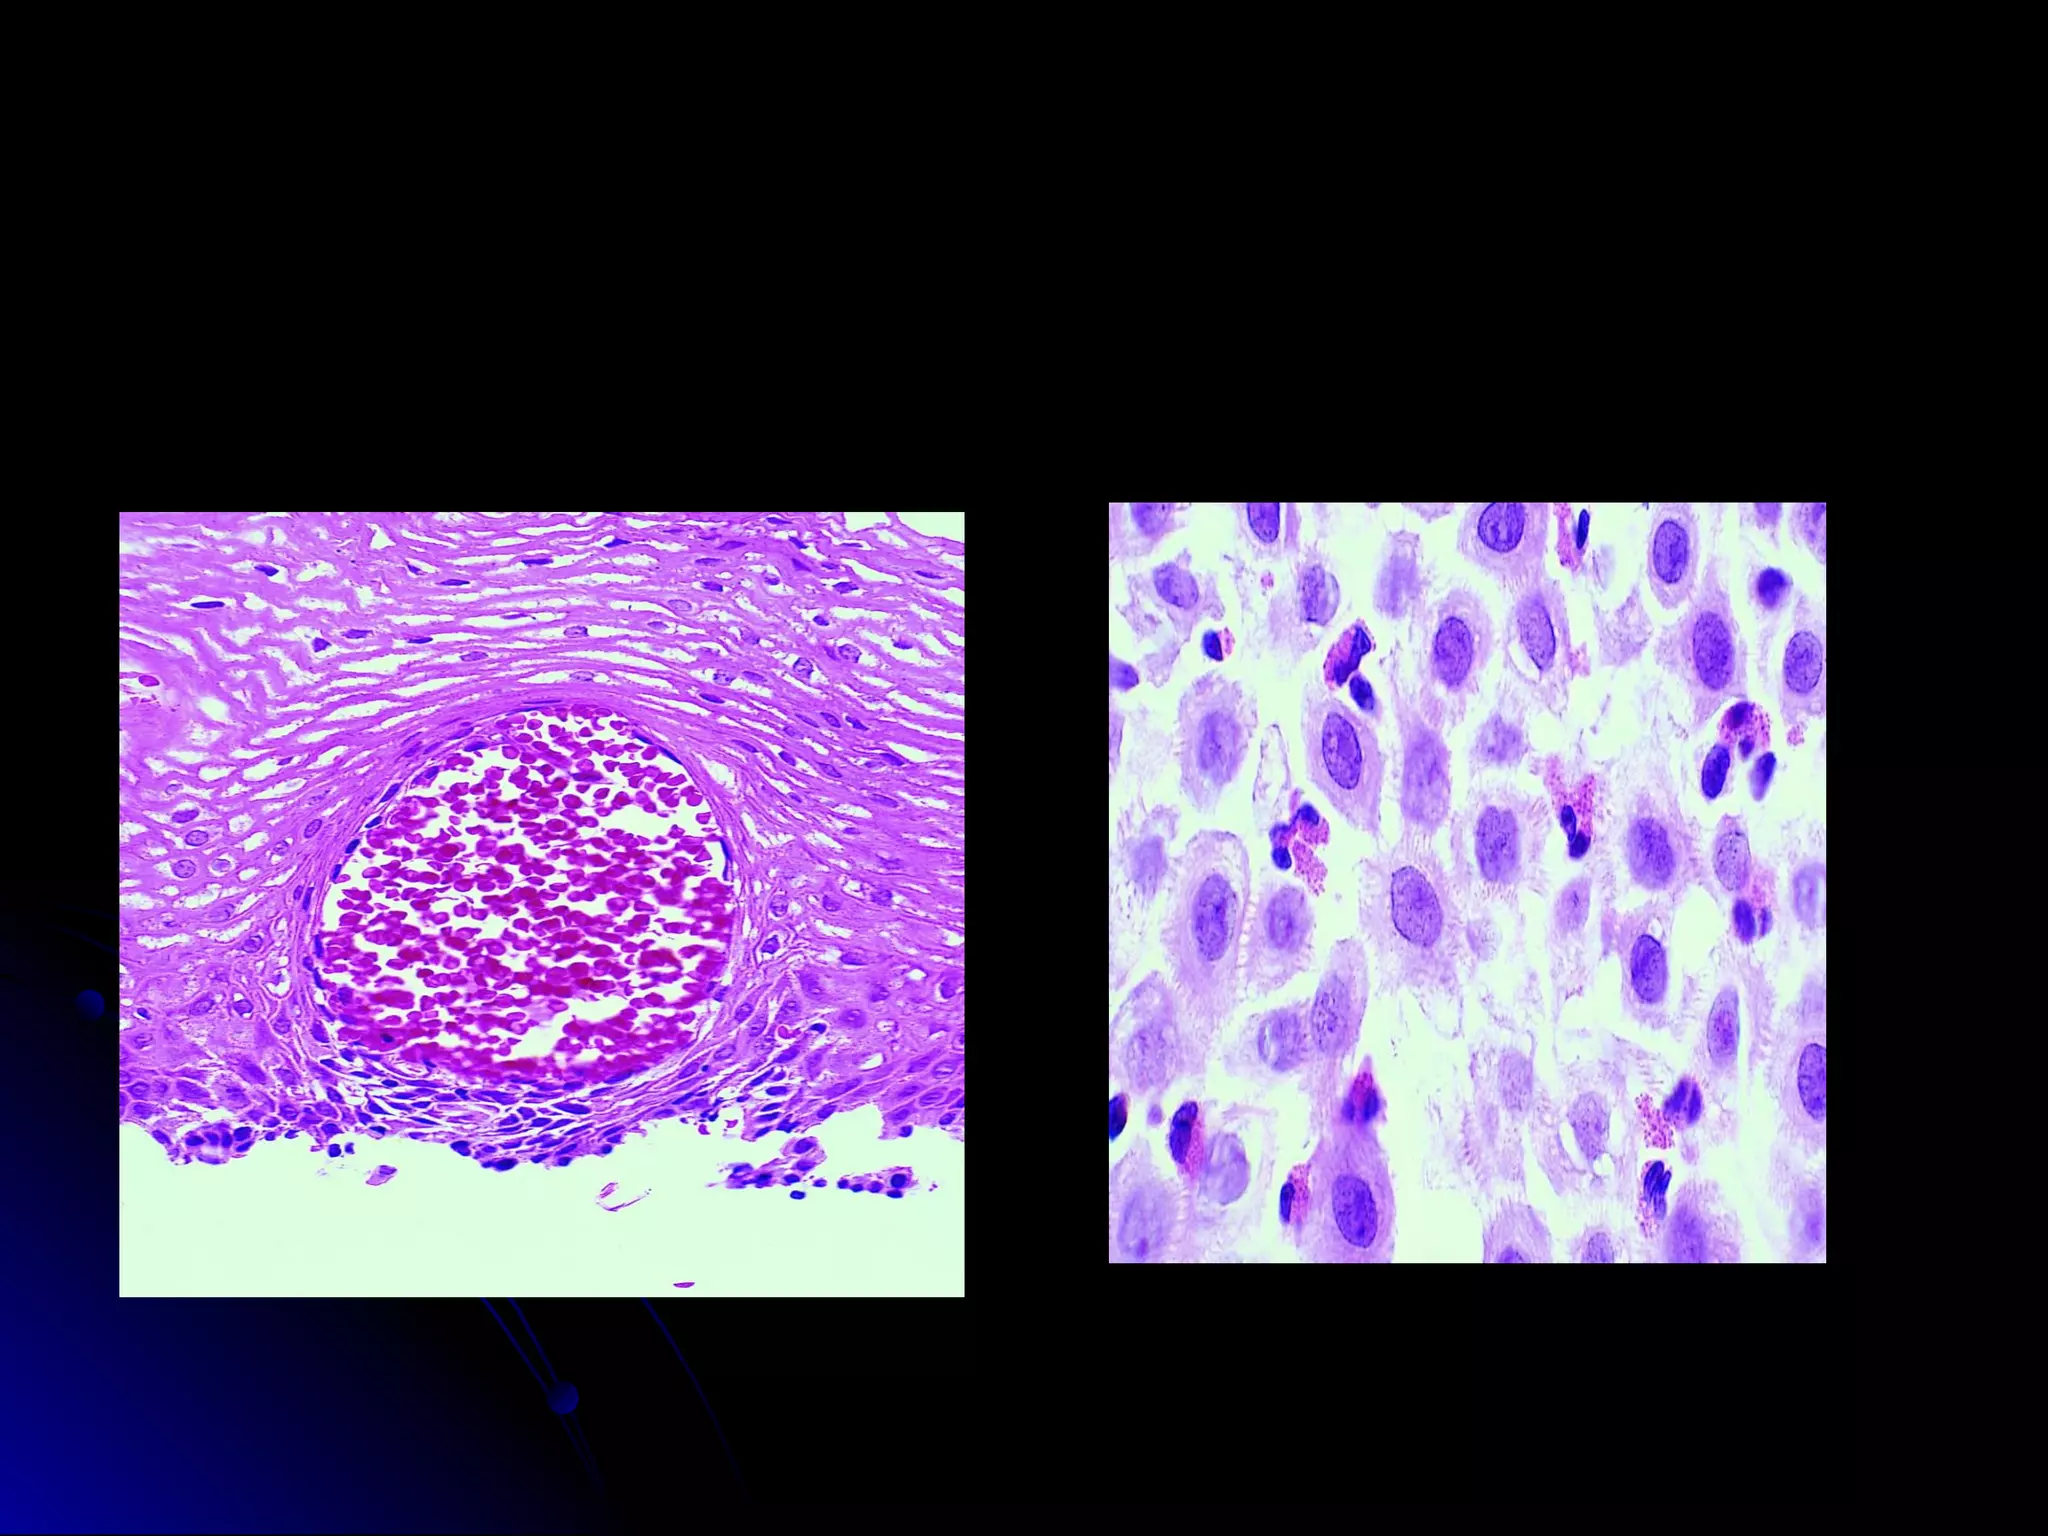

LymphomasLymphomas

Mucosa associated lymphoidMucosa associated lymphoid

tumortumor

 Ulcers, enlarged mucosalUlcers, enlarged mucosal

folds, flatfolds, flat

 Features of low grade MALT –Features of low grade MALT –

1. small lympho, small cleaved1. small lympho, small cleaved

cells 2. lymphoid follicles 3.cells 2. lymphoid follicles 3.

neoplastic plasma cells 4.neoplastic plasma cells 4.

lymphoepithelial lesions clusterlymphoepithelial lesions cluster

of 3-4 lymphocytes destroyingof 3-4 lymphocytes destroying

glands(lymphocytic gastritis –glands(lymphocytic gastritis –

single cells in epi) 5. dutchersingle cells in epi) 5. dutcher

bodies –pas +ve intranuclearbodies –pas +ve intranuclear

inclusionsinclusions

 High grade – no LEL, largeHigh grade – no LEL, large

cells vesicular nuclei,cells vesicular nuclei,

prominent nucleoliprominent nucleoli